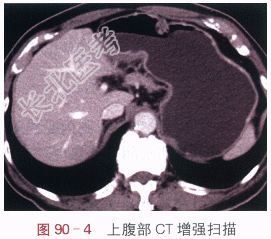

- [材料题] 李某,上腹部疼痛1月,饥饿时明显,饮食可减轻。体格检查:腹部无压痛,未触及肿块。影像学资料:如图90-1~图90-4所示。

- 简答题1、该患者的诊断是什么?其影像学表现有哪些?